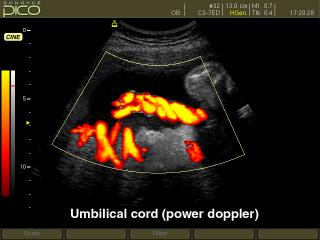

- CFM - цветное допплеровское картирование;

- PD - энергетический допплер;

- CAFE (Compound Automatic Flash Elemination) - обеспечивает зависимую от используемого режима нелинейную фильтрацию для удаления цветных точек на изображении, возникающих из за мерцающих артефактов. Создает улучшенную визуализацию кровотока во всех допплеровских режимах.

Акушерские исследования (плод, сердце плода), гинекология (матка, яичники), абдоминальные исследования (печень, желчный пузырь, поджелудочная железа, селезенка, глубокие сосуды), почки.